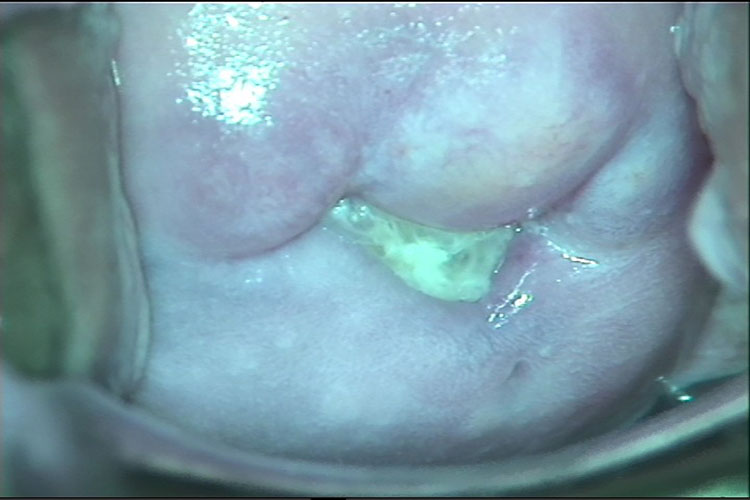

包括滴虫性阴道炎、外阴阴道假丝酵母菌病、细菌性阴道病、萎缩性阴道炎。主要症状是阴道分泌物增多及外阴、阴道瘙痒,患有此病的部分女生会出现灼热、疼痛、同房痛等。分泌物除增多外,性状也会发生变化,可呈灰白色、黄白色、黄绿色等,可为凝乳状或豆腐渣样、泡沫状,并且有异味,比如鱼腥臭味。